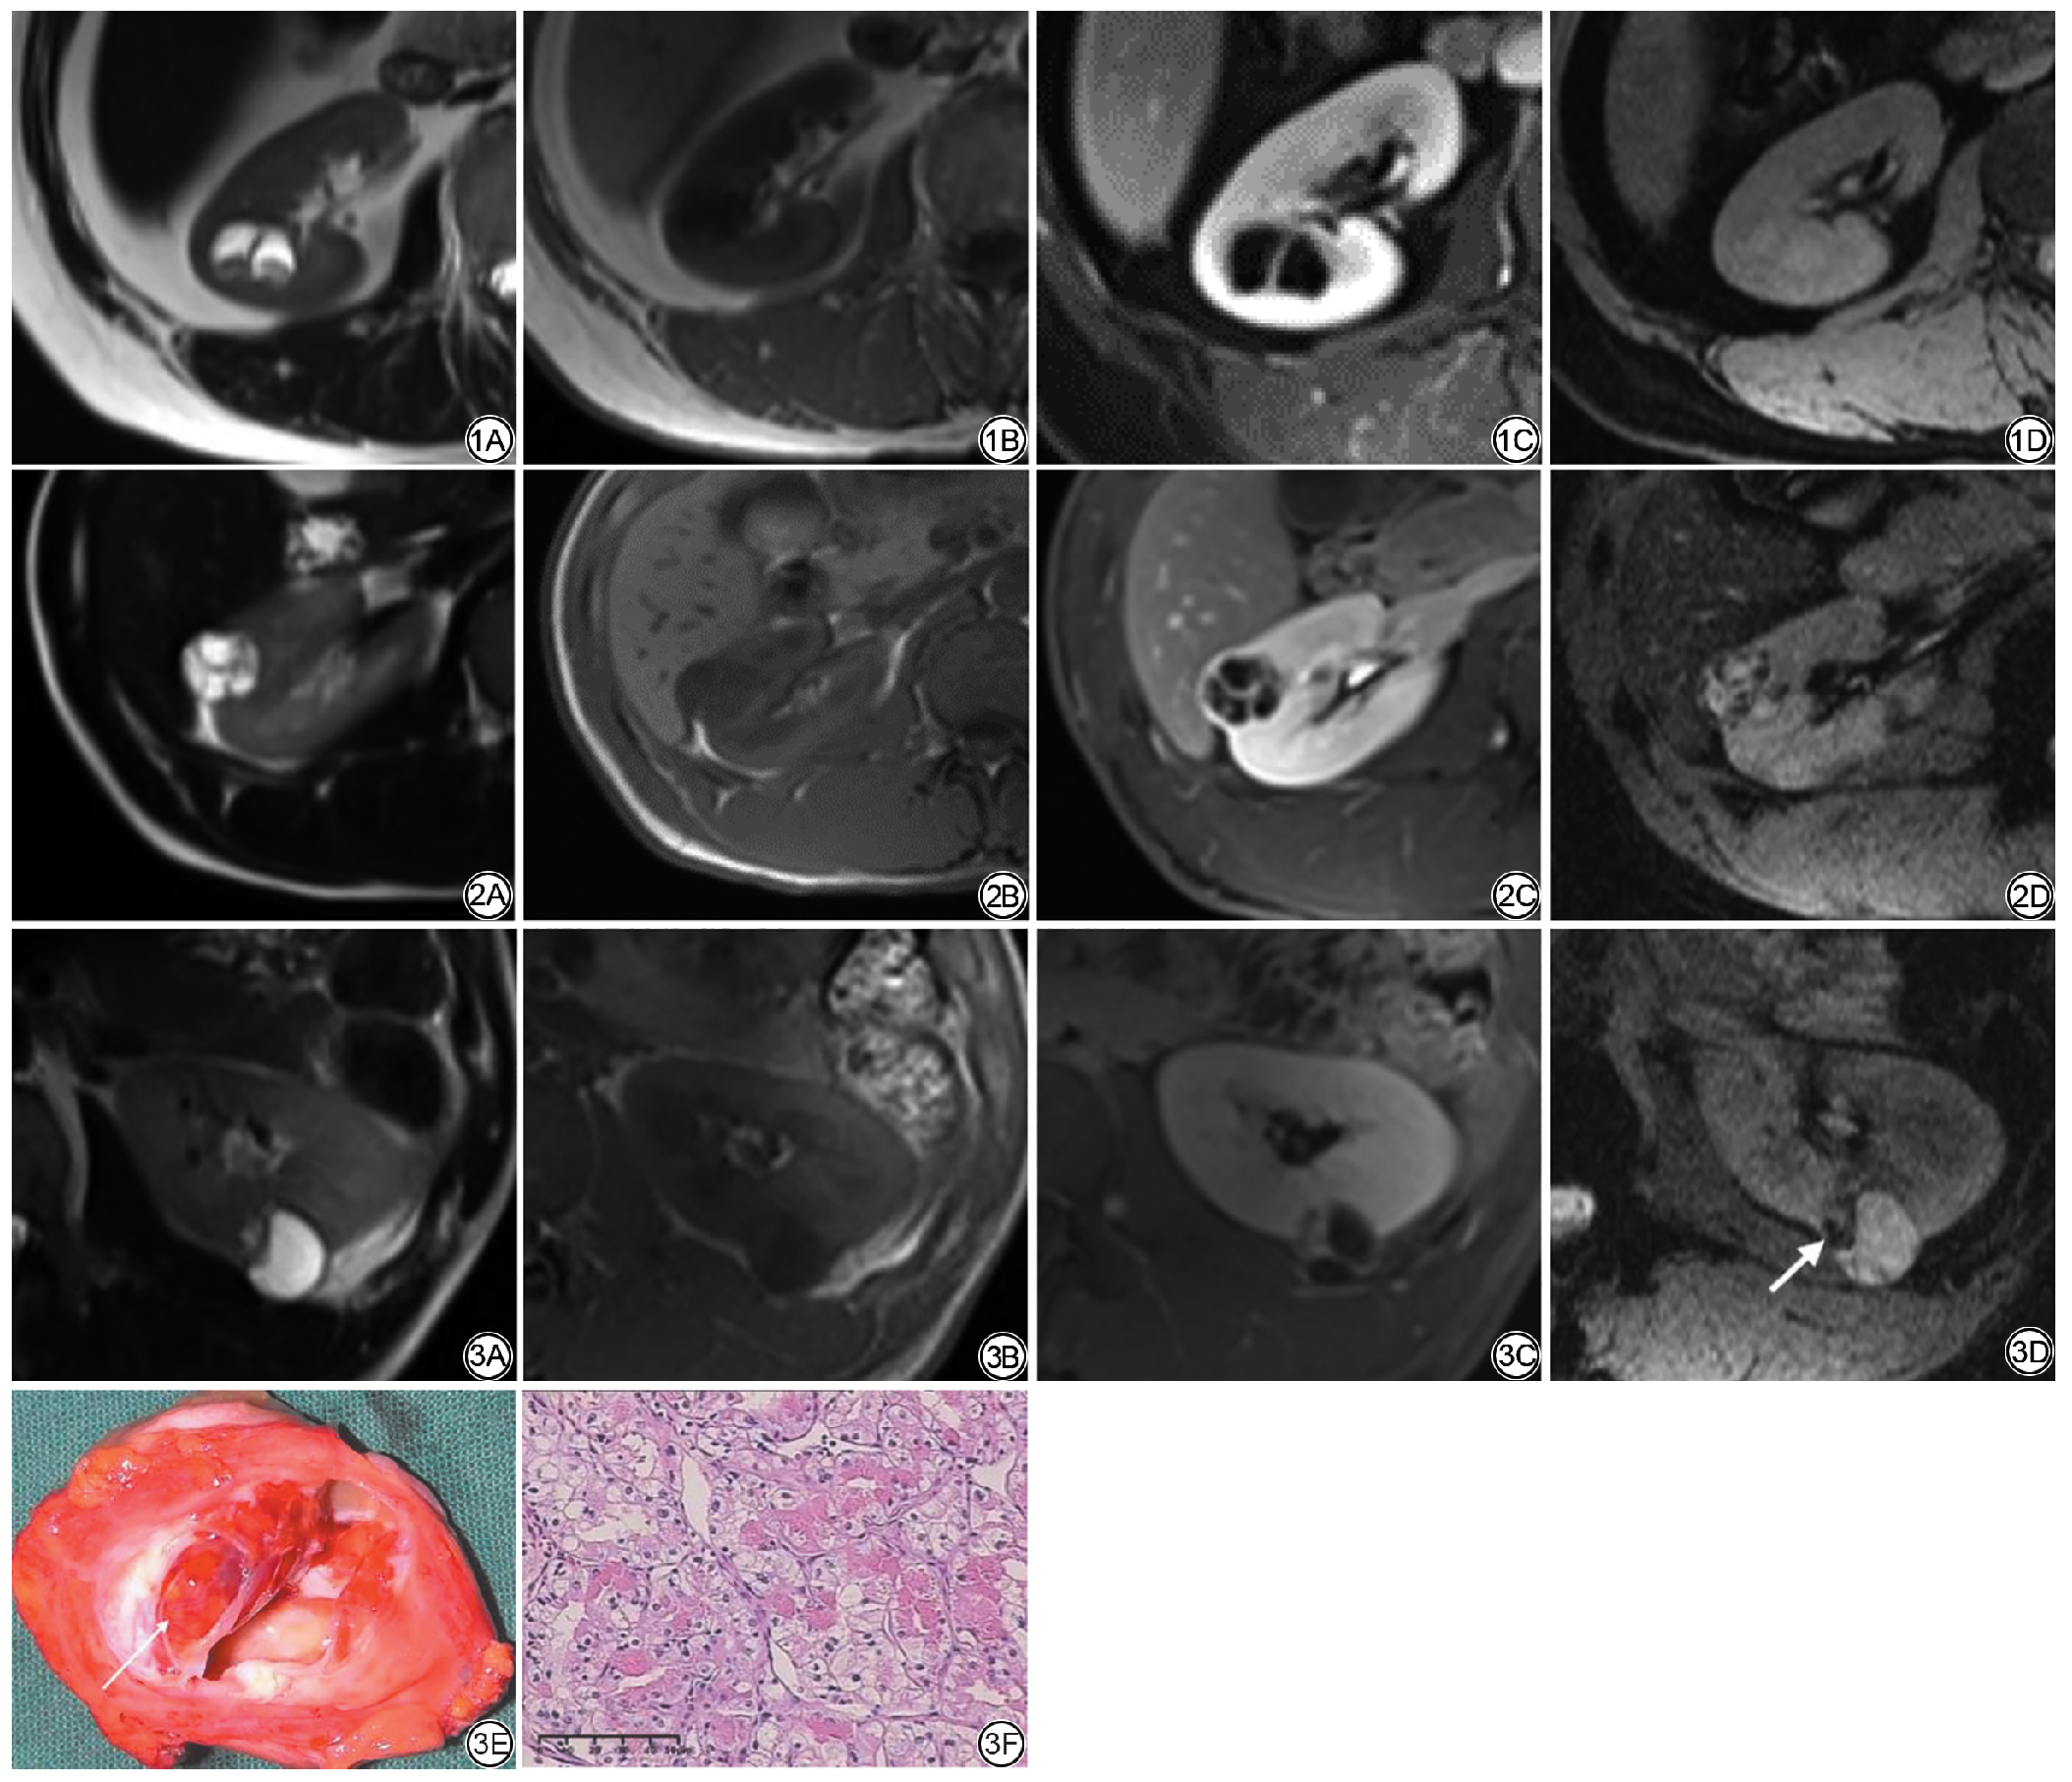

良性组的ITSS主要结构的评级中位数高于恶性组,但二者差异无统计学意义(P>0.05);两组病变出血灶数目评级中位数均为1,但恶性组的上四分位数更高,且分布更集中,提示恶性组中病例的等级更高,差异具有统计学意义(P=0.02);恶性组的微血管数目及实性成分中ITSS所占面积比评级的中位数均高于良性组,且二者差异具有统计学意义(P<0.01);详见表4。恶性组病例的囊壁及分隔中表现出更多的出血灶及微血管结构(图1, 图2, 图3)。

图1  女,58岁,体检发现右肾囊性病变,术后病理:右肾囊肿。1A:T2WI示病灶整体呈高信号,内见等信号结节与分隔;1B:T1WI示病灶整体呈低信号;1C:T1WI增强扫描可见病变内部强化的分隔,结节未见强化;1D:SWI示病变内未见斑点状、线条异常低信号。

图2  男,29岁,体检发现右肾囊性病变,术后病理:右肾囊性肾癌。2A:T2WI示病灶整体呈高信号,内见多发等信号分隔;2B:T1WI示病灶整体呈低信号;2C:T1WI增强扫描可见病变内部多条强化的分隔;2D:SWI示病变内细线样低信号,考虑为病变内的微血管成分。

图3  男,48岁,体检发现左肾囊性占位。3A:T2WI可见病灶整体为高信号,内见低信号分隔;3B:T1WI示病灶整体呈低信号,边缘可见条片状稍高信号;3C:T1WI增强扫描可见病变内部强化的纠集分隔;3D:SWI示病变斑片状低信号,考虑为病变内出血灶(箭);3E:病变内出血灶与SWI图像上低信号区域相对应(箭);3F:病理(HE 10×40)显示细胞巢状条索状分布,胞质透明,核见轻度异型,可见核仁,局灶见出血。SWI:磁敏感加权成像。

Fig. 1  Female, 58 years old, physical examination revealed cystic lesions in the right kidney, postoperative pathology : right renal cyst. 1A: T2WI shows that the lesion as a whole presented hyperintense, with isosignal nodules and separations observed internally; 1B: T1WI shows that the lesion as a whole presented a low signal; 1C: T1WI enhanced scan shows the separation of internal enhancement of the lesion; 1D: SWI shows no abnormal low signal in the lesion.

Fig. 2  Male, 29 years old, physical examination revealed cystic lesions of the right kidney, postoperative pathology: cystic renal cell carcinoma of the right kidney. 2A: T2WI shows that the lesion as a whole presented a high signal, and multiple signal separations are observed within. 2B: T1WI shows that the lesion as a whole presented a low signal; 2C: T1WI enhanced scan shows multiple enhanced separations within the lesion; 2D: SWI shows a thin line-like low signal in the lesion, which is considered to be the microvascular component in the lesion.

Fig. 3  Male, 48 years old, physical examination revealed cystic mass in the left kidney. 3A: On T2WI, the whole lesion show high signal intensity with low signal separation; 3B: T1WI shows that the lesion is hypointense, and the edge is patchy and slightly higher; 3C: T1WI enhanced scan shows the separation of internal enhancement of the lesion, and the separation edge is blurred; 3D: SWI shows patchy low signal of the lesion, which is considered as hemorrhage in the lesion; 3E: The hemorrhage in the lesion corresponded to the low signal area on the SWI image (arrow). 3F: Pathology (HE 10×40) shows that nest-like cord-like distribution of cells, transparent cytoplasm, mild nuclear atypia, visible nucleoli. SWI: susceptibility-weighted imaging.